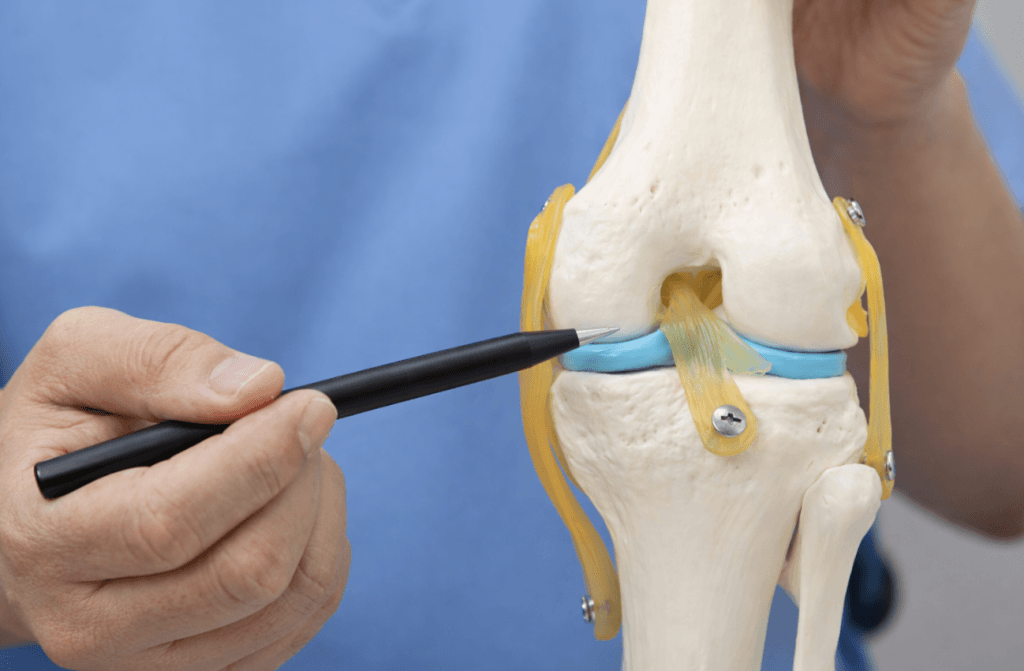

What Type of Surgery Is Performed?

If surgery is required, there are two main approaches:

Meniscus Repair

- The torn meniscus is stitched back together

- Preferred when possible

- Helps preserve long-term knee health

Partial Meniscectomy (Trimming)

- The damaged portion is removed

- Used when the tear is not repairable

Where possible, preserving the meniscus is always preferable, as loss of meniscal tissue can increase the risk of osteoarthritis over time. See meniscal repair for more information about meniscus surgery.